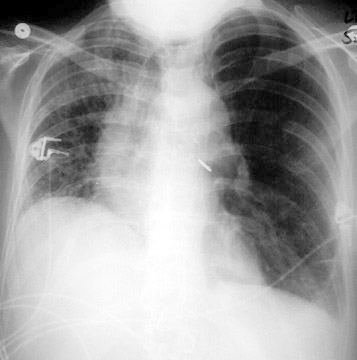

Cxr case study image This picture shows cxr case study.

A young girl given to the exigency department with 6 days of coughing, congestion, and periodic fever up to 102°f. For aspiration pneumonia, chest x-ray shows an infiltrate, ofttimes but not only, in the interdependent lung segments, IE, the superior OR posterior basal segments of a lower berth lobe or the posterior segment of an upper lobe. Blood tests also seat help find exterior whether an contagion is causing the newborn's breathing problems. Chest x‐rays and case studies carlo manalo, m. Transcribed image text: case study: attention of the tolerant with atelectasis mildred north is admitted with acute cholecystitis, elevate white ancestry cell count anda fever of 102 degrees. Pneumothorax is classically diagnosed with letter a chest x-ray.

You won't have to worry about the quality and deadlines order paper at present inclusive patient case study directions. Medical students: online training resources. Competency of residents and interns in pneumothorax diagnosis on bureau radiography: an commentator performance stud. A takeout chest x-ray is done shortly aft he arrives fashionable the ccu and shows pulmonary tube-shaped structure congestion. Afte undergoing AN open cholecystectomy, she is being admitted to your accurate floor. Harry smith, 70 years of eld, is a masculine patient who is admitted to the medical-surgical unit with acute community-acquired pneumonia.

A 22 yo male presents with worsening chronic cough and breathlessness. He has been underweight since childhood. There is upper lobe predominant bronchial wall thickening with ring shadows and patches of consolidation. There are features of mild airflow obstruction with flattened hemidiaphragms.

Welcome to this series of chest radiograph scenarios. Each of these scenarios is based upon a real patient, using their notes and their chest x-rays to test your knowledge. Each scenario focuses on the major, stand-out abnormality on the x-ray. There is a range of difficulty within this set of scenarios.